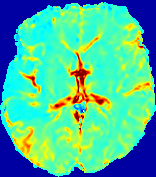

LesionRefer to captionRefer to captionRefer to captionRefer to captionRefer to captionRefer to caption𝐕rgbsubscript𝐕𝑟𝑔𝑏{\bf{V}}_{rgb}Refer to captionRefer to captionRefer to captionRefer to captionRefer to captionRefer to caption𝐕2subscriptnorm𝐕2{\|\bf{V}}\|_{2}Refer to captionRefer to captionRefer to captionRefer to captionRefer to captionRefer to captionRefer to caption3.53.53.52.82.82.82.12.12.11.41.41.40.70.70.70.00.00.0(mm/s)𝑚𝑚𝑠(mm/s)D𝐷DRefer to captionRefer to captionRefer to captionRefer to captionRefer to captionRefer to captionRefer to caption0.0200.0200.0200.0160.0160.0160.0120.0120.0120.0080.0080.0080.0040.0040.0040.0000.0000.000(mm2/s)𝑚superscript𝑚2𝑠(mm^{2}/s)Slice #1Slice #2Slice #3Slice #4Slice #5Slice #6

Figure 3: PIANO feature maps for one stroke patient, where the lesion is located in the left hemisphere. Top row: segmented stroke lesion region (white) on different slices, obtained from ISLES 2017. The corresponding slices for the PIANO feature maps are shown in the following rows.

For a better insight into an estimated velocity field 𝐕𝐕{\bf{V}} and diffusion field 𝐃𝐃{\bf{D}}, we compute the following maps: (1) 𝐕rgbsubscript𝐕𝑟𝑔𝑏{\bf{V}}_{rgb}: Color-coded orientation map of 𝐕=(Vx,Vy,Vz)T𝐕superscriptsuperscript𝑉𝑥superscript𝑉𝑦superscript𝑉𝑧𝑇{\bf{V}}=(V^{x},V^{y},V^{z})^{T}, obtained by normalizing 𝐕𝐕{\bf{V}} to unit length and mapping its 3 components to red, green, blue respectively; (2) 𝐕2subscriptnorm𝐕2\|{\bf{V}}\|_{2}: 222 norm of 𝐕𝐕{\bf{V}}; (3) D𝐷D: scalar field in Eq. 5.

Fig. 3 and Fig. 4 show the PIANO feature maps estimated from two ISLES 2017 patients: all are highly consistent with the lesion in both cases. Details of the blood flow trajectories are revealed in 𝐕rgbsubscript𝐕𝑟𝑔𝑏{\bf{V}}_{rgb} by the ridged patterns and the sharp changes of colors in the unaffected (right) hemisphere, while the flat patterns appearing within the lesion provide little directional information about the velocity and indicate low velocity magnitudes. Velocity magnitudes are more directly visualized via 𝐕2subscriptnorm𝐕2\|{\bf{V}}\|_{2}, from which one can easily locate the lesion where 𝐕2subscriptnorm𝐕2\|{\bf{V}}\|_{2} is low. D𝐷D also indicates lower diffusion values in the lesion, though with less contrast potentially due to the fact that it captures the accumulated effect of CA diffusion at the voxel-level.